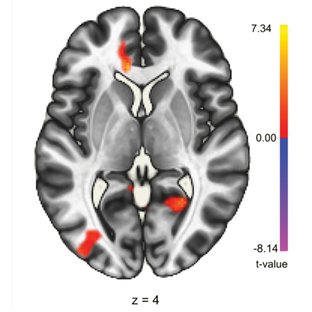

Junto com outros investigadores, há anos que Dawson Church procurava uma forma de tornar fácil a prática de meditação para iniciantes. Estudaram o cérebro e o corpo de meditadores experientes usando para tal ferramentas como eletroencefalogramas e ressonâncias magnéticas e ficaram a saber exatamente como são as suas ondas cerebrais, tónus muscular e padrões de respiração. Descobriram que se uma pessoa sem nenhuma experiência de meditação se sentasse, respirasse e relaxasse exatamente os mesmos músculos que um mestre de meditação, caíam num estado meditativo profundo em 4 minutos ou menos, isto sem nenhum treino ou crença exigidos.

Em 2019, a especialista em EEG Judith Pennington publicou um estudo que mostrou que, em meditadores iniciantes: “ A EcoMeditação produziu níveis extraordinariamente altos de Sincronia Gama… os participantes adquiriram estados cerebrais elevados normalmente encontrados apenas após anos de prática de meditação. A EcoMeditação facilitou a capacidade dos participantes de induzir e sustentar as ondas cerebrais alfa características da integração emocional, mental e espiritual de alto nível.”